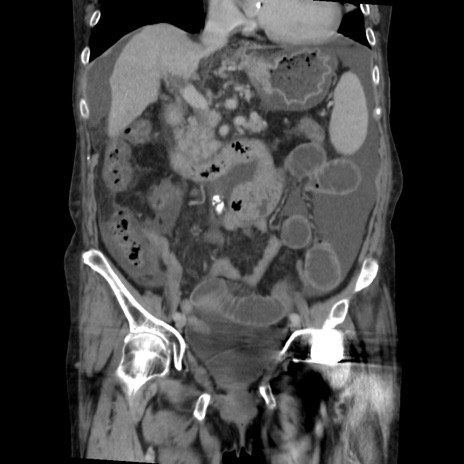

症例31(冠状断像)

【症例】80歳代 女性

【主訴】腹部膨満感

【現病歴】他院にて肝硬変にてフォロー中。1週間前から便秘、腹部膨満感、臍部腫瘤あり受診となる。

【既往歴】肝硬変

【身体所見】腹部膨隆あり、皮膚変化なし、疼痛なし。

【データ】WBC 4600、CRP 0.25